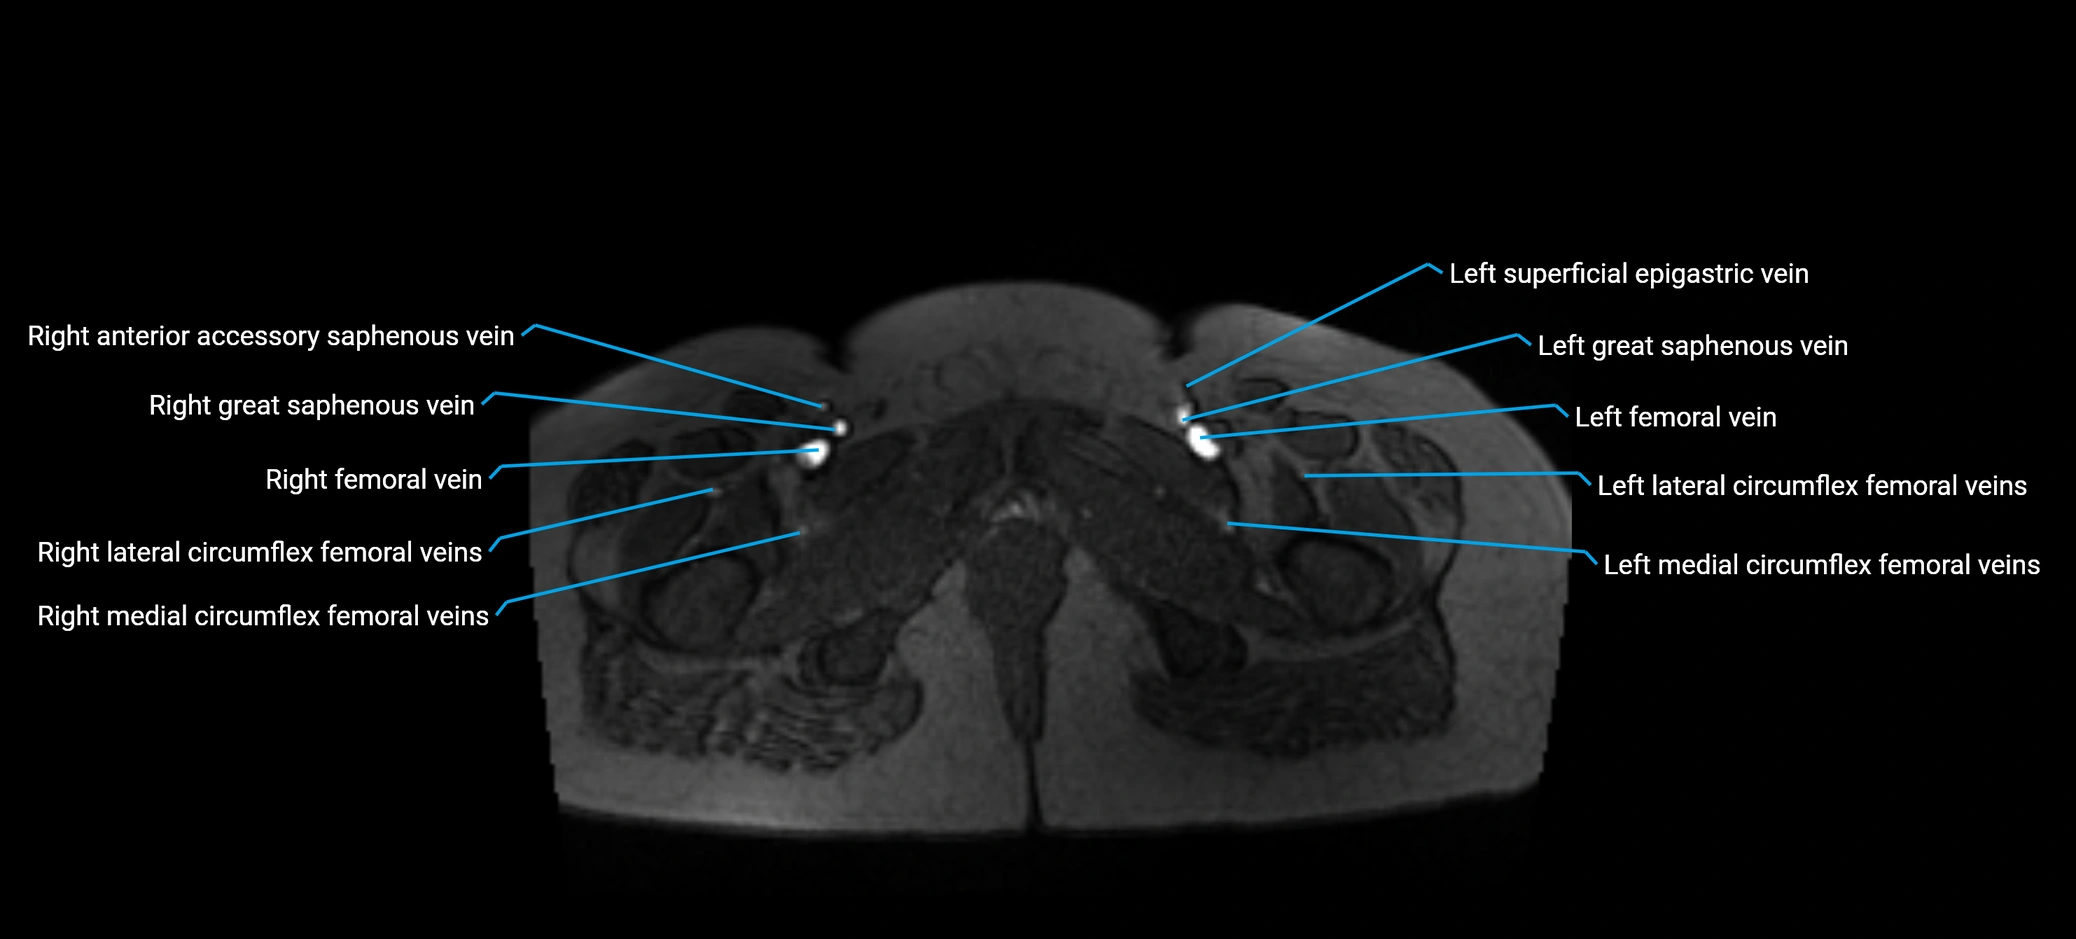

MRI image

image